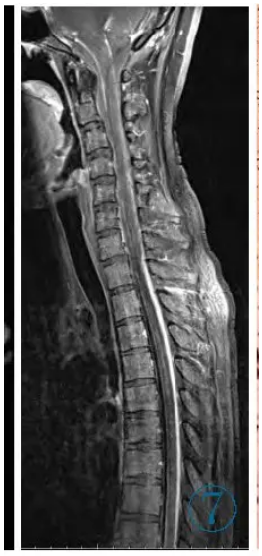

,予抗结核联合糖皮质激素

图7 脊柱增强T1WI同时示软脊膜广泛增厚、强化,以后部明显。